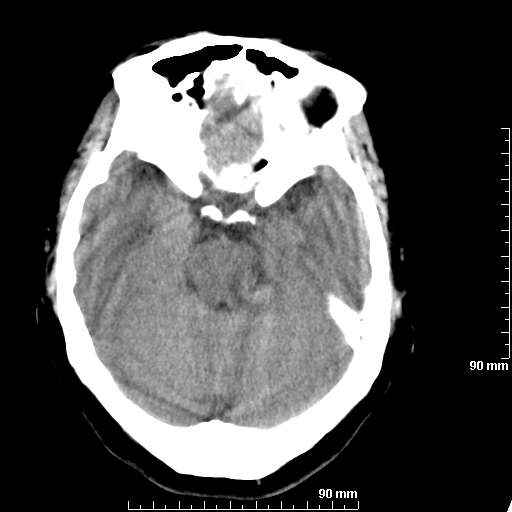

[维修案例解析] 大家猜猜看,这个伪影是怎样产生的.

我院西门子单排CT由于一零件受损而产生的伪影.

哈哈,都不是。是虑线器fiter裂损。大家没想到吧。

哦,跟脑出血有点像哦

形状不规则,边缘模糊。比较特殊的一种伪影哈!

这种伪影很常见!伪影应该是在视野的中心的。

西门子的虑线器fiter裂损这才是很难见的问题,GE的最常见

虑线器老化,中间崩裂一块掉了